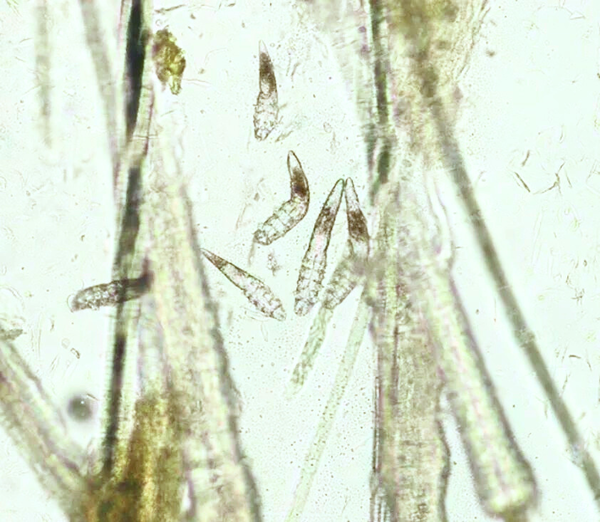

Diagnosi della Demodicosi

La rogna demodettica, nota anche come demodicosi, essendo una malattia della pelle causata da acari microscopici del genere Demodex .

La ricerca di questi acari Demodex e’ la base degli esami diagnostici. Questi esami vengono effettuati nella Clinica Veterinaria Gaia

- Raschiamento cutaneo profondo, per la raccolta di cellule e follicoli piliferi, e esame microscopico